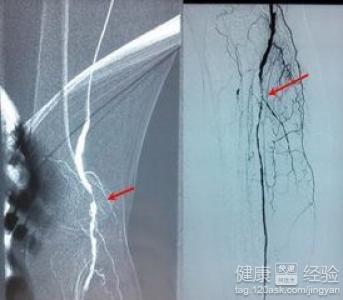

下肢動脈硬化閉塞症是一種常見的全身性疾病,出現這種疾病以後會造成患者有疼痛感,出現下肢動脈硬化閉塞症,經常好發的部位是動脈,主動脈,股動脈,出現動脈硬化會造成,粥樣斑塊,而且還會出現鈣化的表現,那麼就會導致動脈管狹窄形成閉塞的表現,所以我們在生活當中出現了動脈硬化的時候要及時的進行治療,下肢動脈硬化閉塞症有哪些表現呢!

2患者要注意出現了下肢動脈硬化閉塞症之後,會給患者造成很嚴重的後果,出現這種疾病會造成肌肉的疼痛感,患者無法正常的行走而且還會在臨床上發現,動脈出現狹窄和閉塞的情況,這個時候患者常常會感覺到非常的疼痛和麻木。,

3嚴重的下肢動脈硬化閉塞症會造成患者,出現潰瘍壞死的症狀而且嚴重的會造成肢體的慢性缺血,無法正常的站立行走,會在夜間無法正常的入睡,會對睡眠造成很嚴重的後果還會出現缺血性潰瘍疾病出現感染。